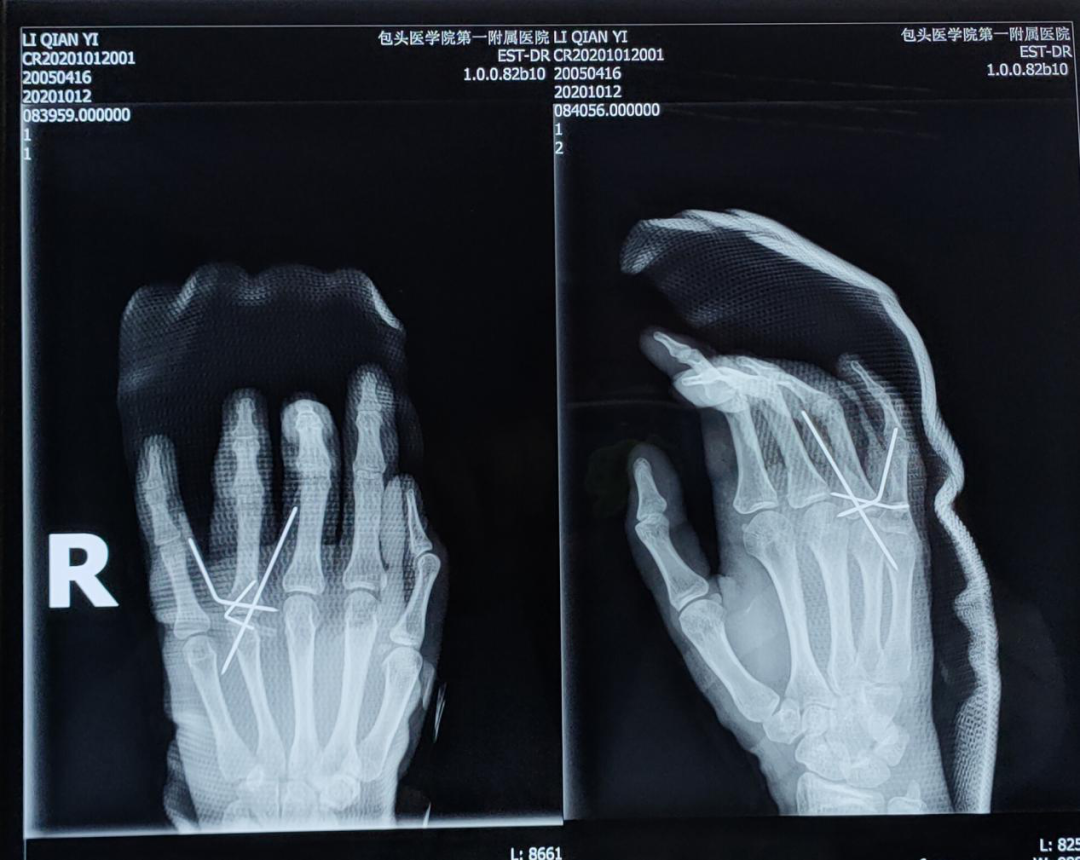

在完成相关检查后,小李被确诊为单指不全切断、开放性指骨骨折、手部指屈肌腱损伤等,手足踝外科医生连建强与同事们迅速为小李制定了手术计划,通过严谨细致的手术治疗,小李受伤的手部慢慢得到了恢复,骨折处复位良好,手指可轻微活动。目前,小李已在家属的陪伴下顺利出院,在家进行休养。